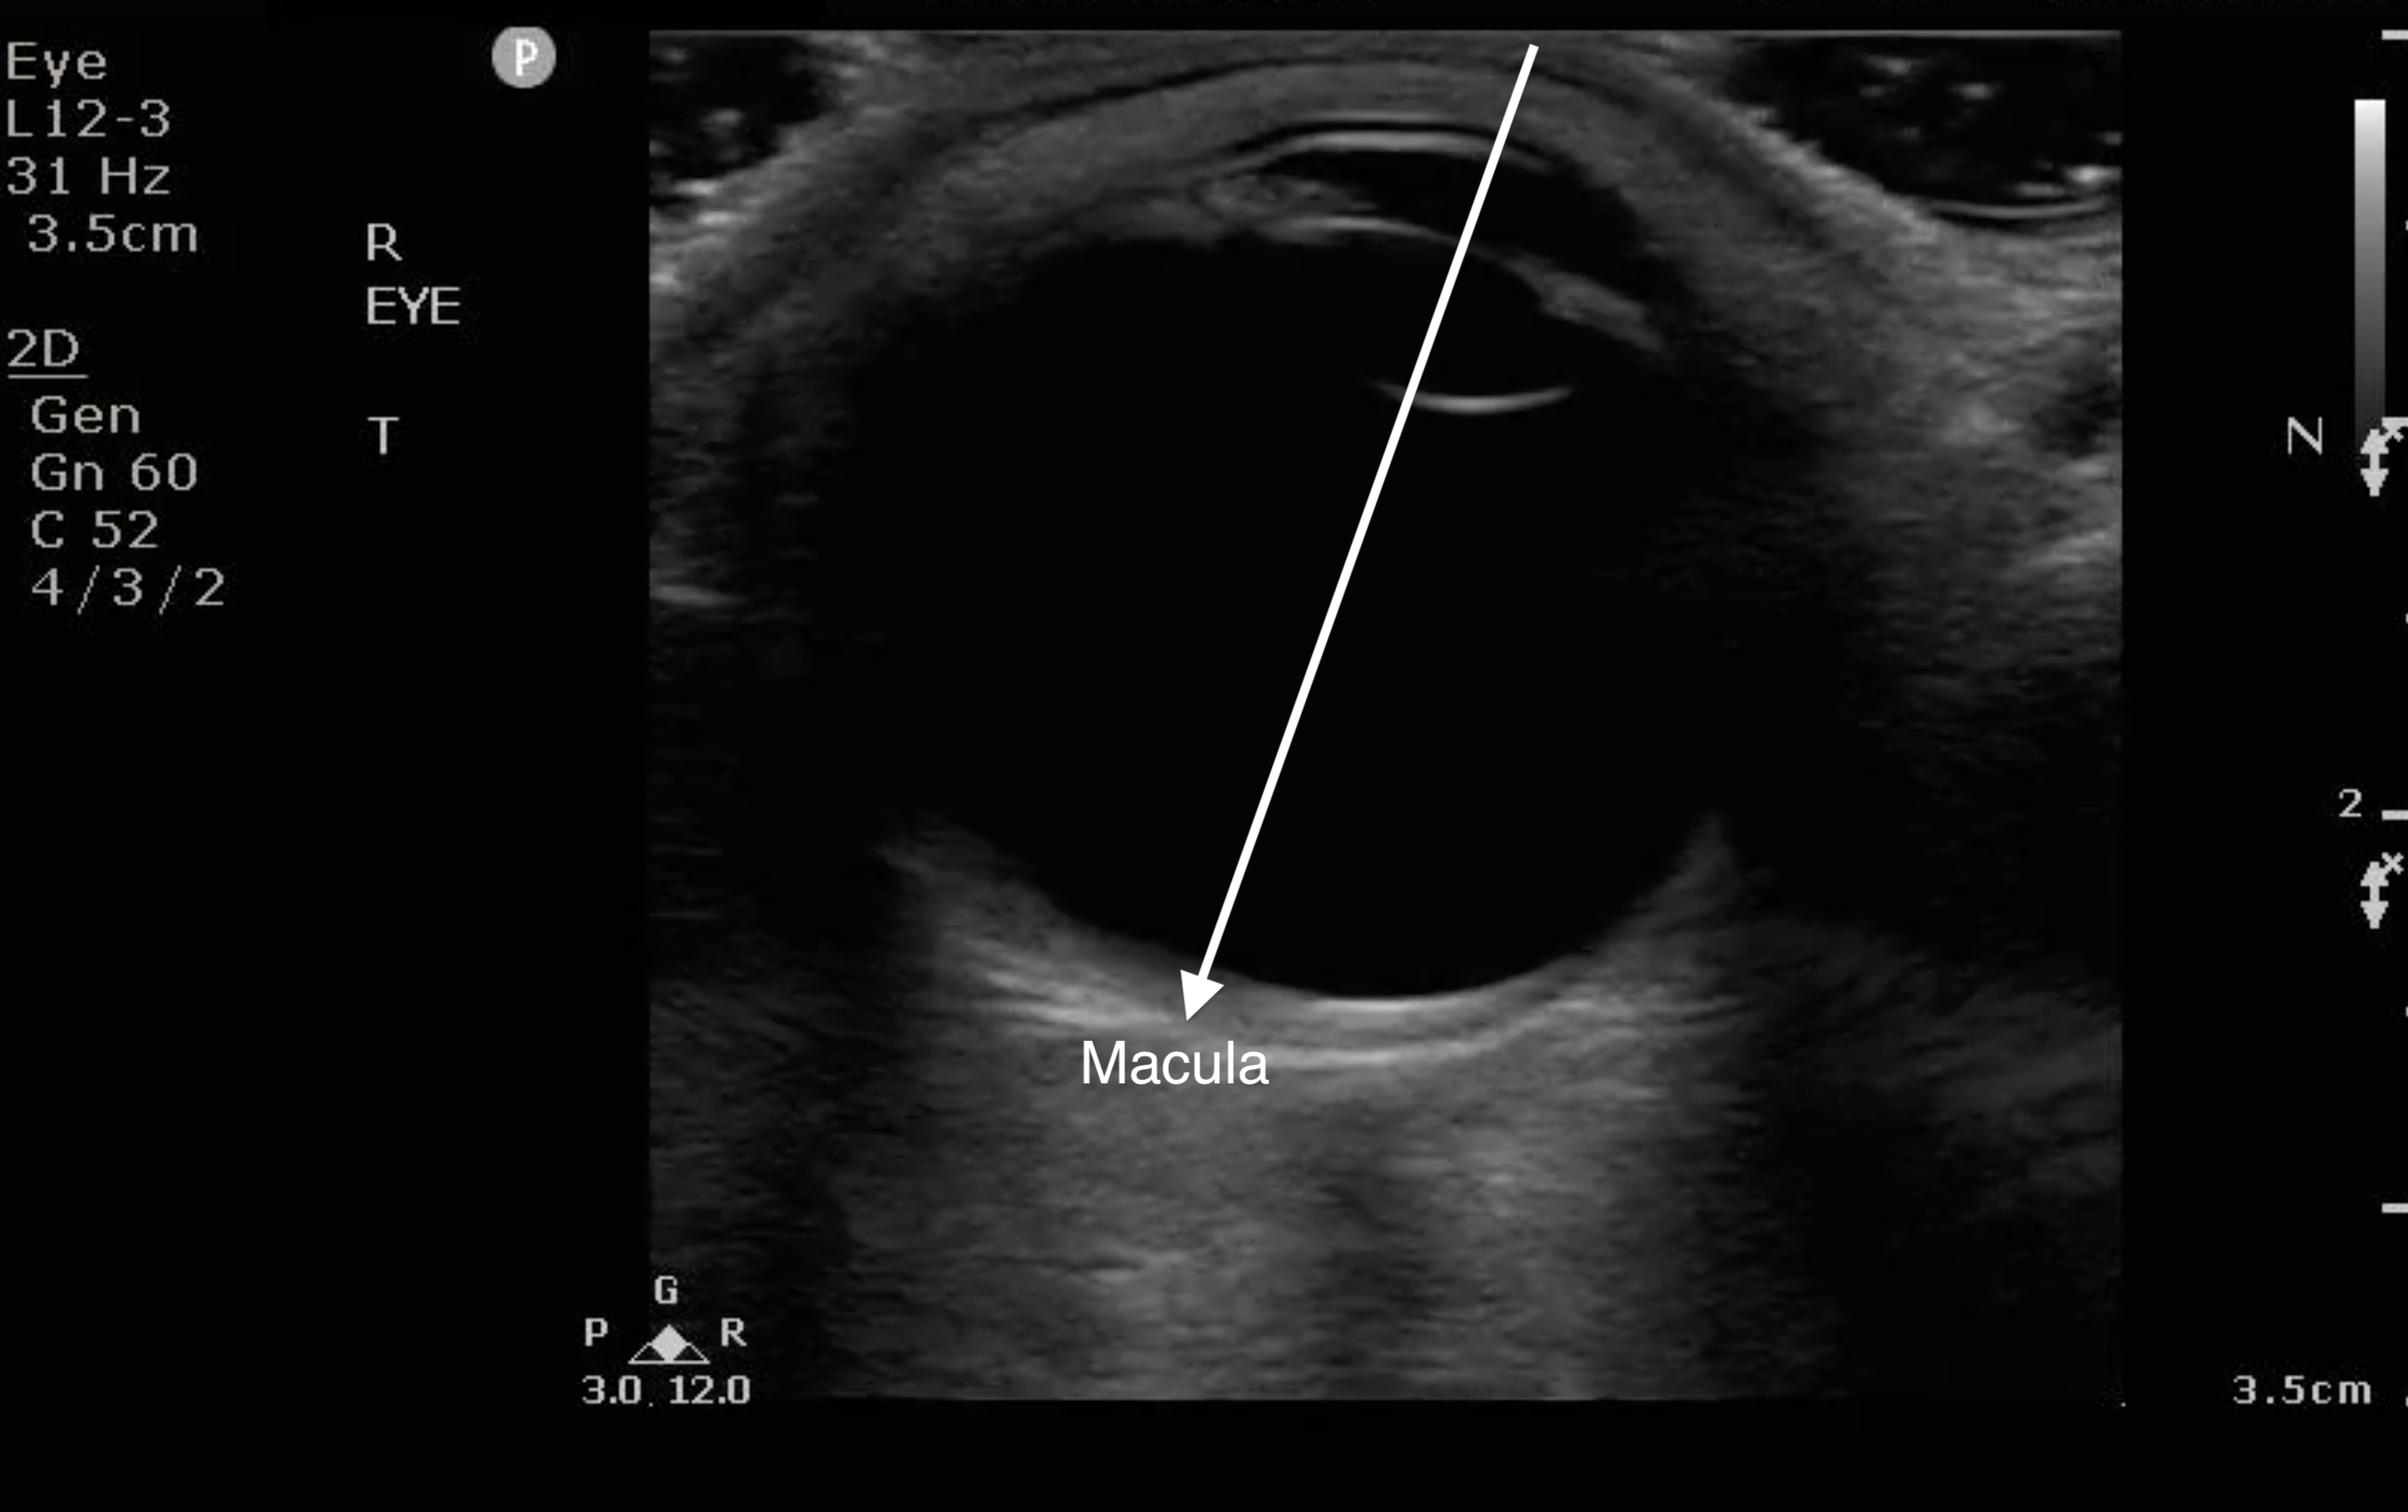

- The macula is temporal to the optic nerve. It cannot be visualized sonographically though location can be approximated by the location of lens (see Fig. 8). If the RD extends temporally from the base of the optic nerve, it can be assumed that it has come off of the macula (“mac off retinal detachment”).

- Figure 8. When the anterior chamber is lined up with the lens, draw a line to bisect the globe to the back on the temporal side. That is where the macula is located.